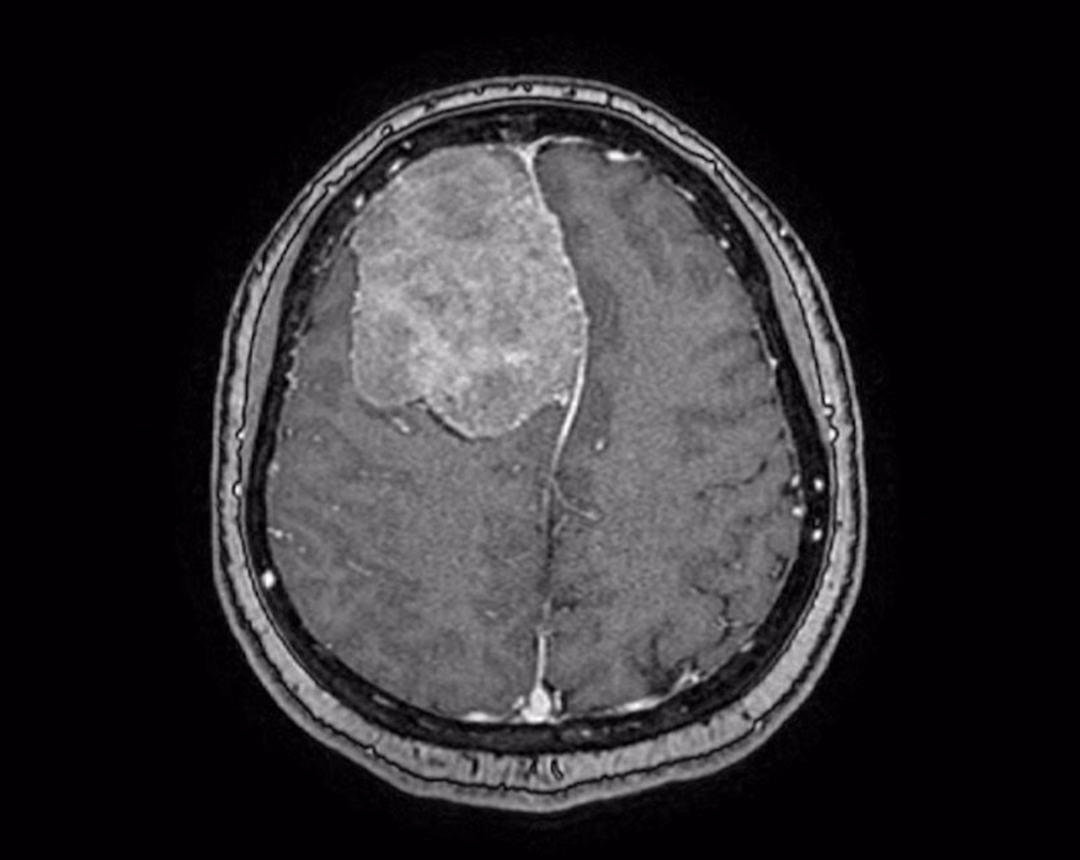

Chị Trịnh Nhật Khánh, một nữ võ sư 45 tuổi đang sinh sống tại TP.HCM, là bệnh nhân thực hiện ca phẫu thuật này. Khối u màng não rất lớn của chị Khánh đã được phát hiện trong quá trình tầm soát đột quỵ tại Bệnh viện FV. Các bác sĩ đã xác định rằng khối u này chèn ép gần 1/4 não và cần phải được loại bỏ sớm để tránh những biến chứng nguy hiểm có thể xảy ra.

Trước khi tiến hành phẫu thuật, các bác sĩ đã lên kế hoạch chi tiết, bao gồm cả việc thuyên tắc mạch máu nuôi khối u. Mục đích của bước này là giảm thiểu rủi ro mất máu trong quá trình phẫu thuật. Song song đó, bệnh viện cũng đã sử dụng hệ thống định vị dẫn đường thần kinh Navigation và hệ thống cắt đốt u bằng siêu âm. Đây là những công nghệ hiện đại giúp đảm bảo ca phẫu thuật được thực hiện thành công và an toàn.